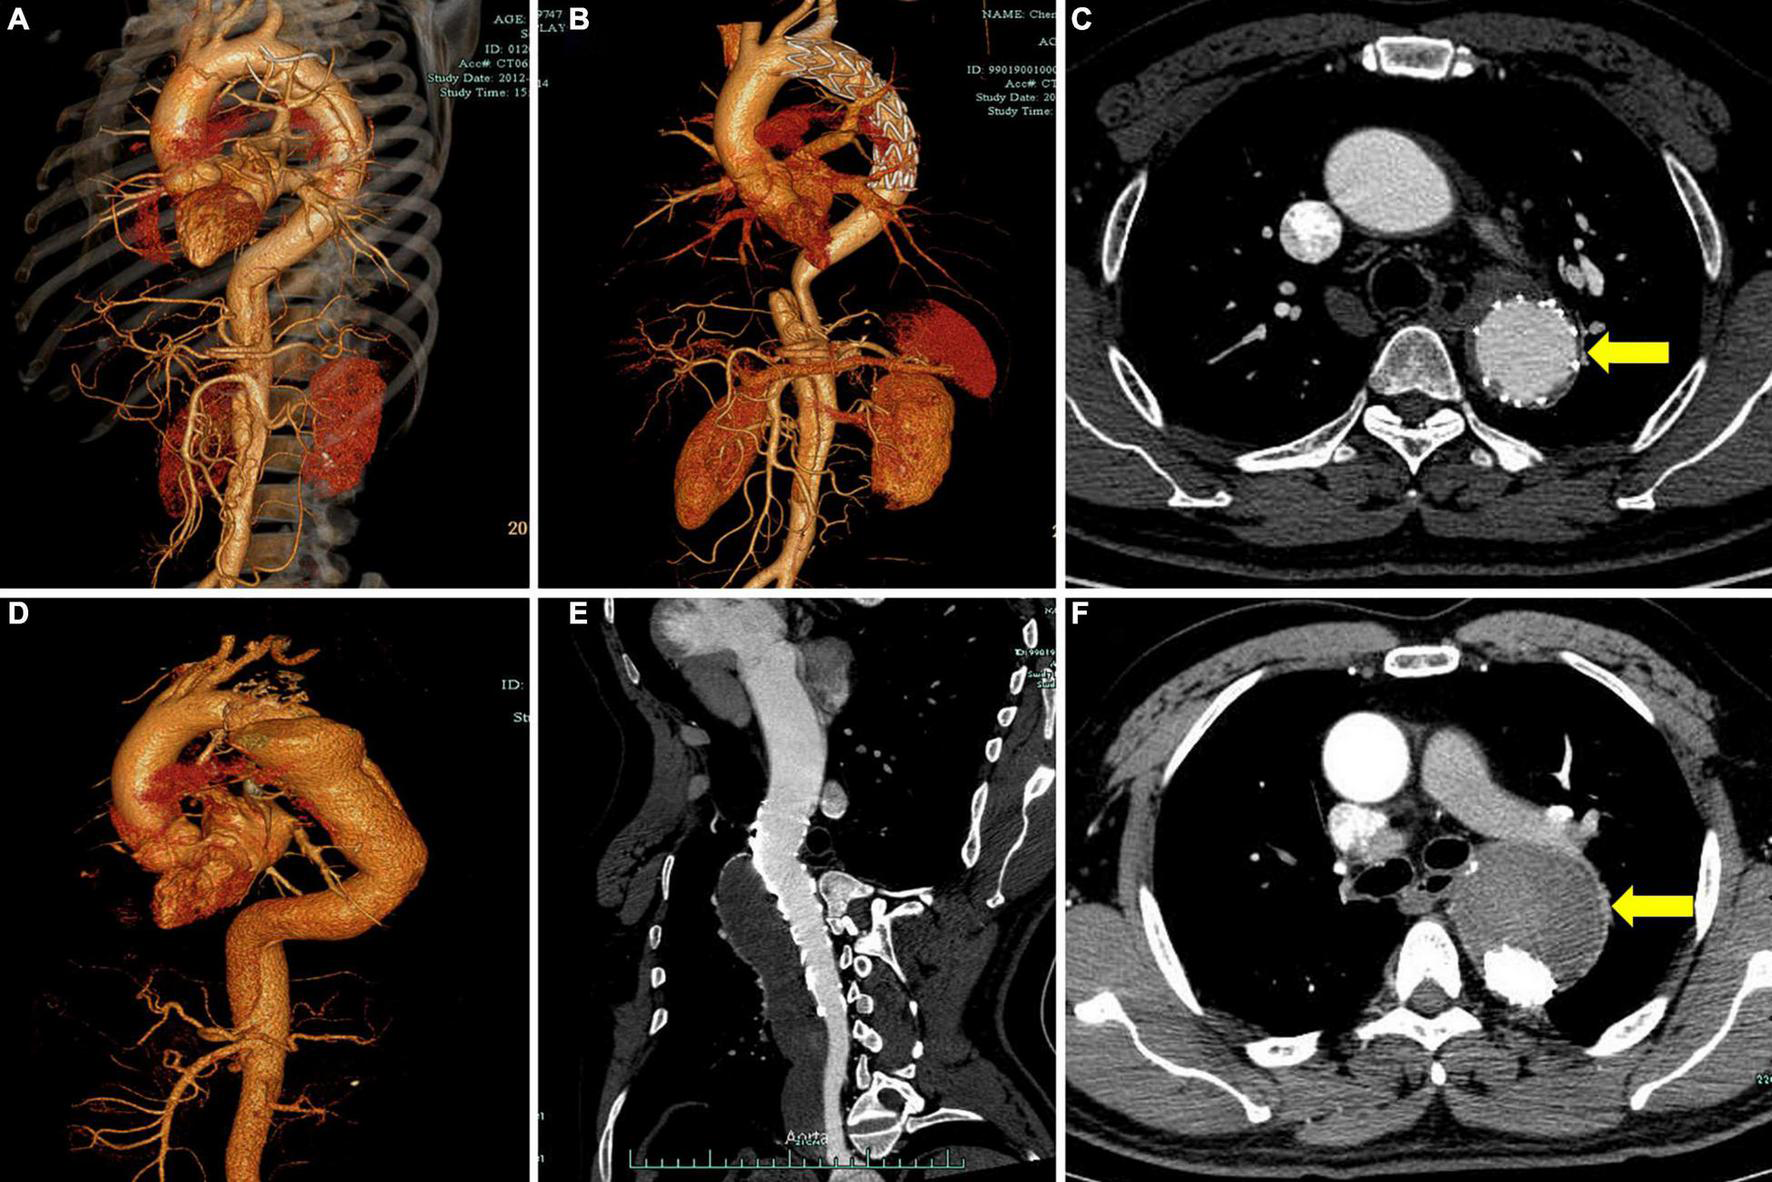

FIGURE 2

Representative cases of different degrees of FL thrombosis after TEVAR. Computed tomography angiography (CTA) images show the FL status of a patient with subacute aortic dissection before operation (A) and 2 years after TEVAR (B). The cross-sectional image shows complete obliteration of FL (C, yellow arrow). CTA images show the FL status of a patient with chronic aortic dissection before operation (D) and 2 years after TEVAR (E). The cross-sectional image shows total FL thrombosis (F, yellow arrow). FL, false lumen; TEVAR, thoracic endovascular aortic repair.